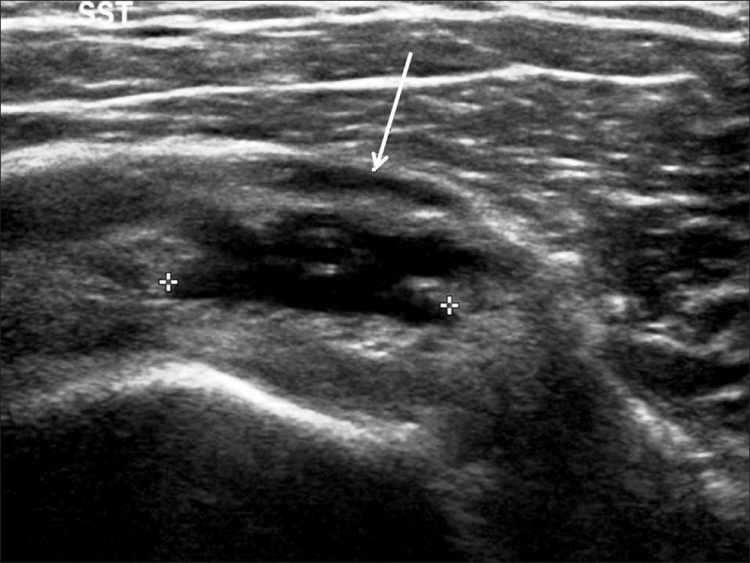

Los desgarros del manguito de los rotadores son la patología más común que se encuentra en los exámenes de ultrasonido del hombro.[7] La incidencia de lágrimas aumenta con la edad. Los desgarros de tendones se pueden clasificar de acuerdo con el grado de falla de la fibra, que van desde desgarros completos [Figura 7], desgarros de espesor total [Figuras 8, 9], desgarros de espesor parcial [Figuras 10-12] y desgarros intrasustancia [Figura 13 ]. Un desgarro agudo suele ir acompañado de derrame articular o bursal [Figura 12]. [7-9] La ausencia de derrame generalmente se relaciona con desgarros crónicos.[9] En un metanálisis sobre la precisión de la resonancia magnética, la artrografía por resonancia magnética y la ecografía en el diagnóstico de desgarros del manguito de los rotadores, la ecografía ofreció una alta sensibilidad y especificidad para la evaluación de los desgarros del manguito de los rotadores de espesor total (92,3 y 94,4 %, respectivamente) con 85,1 % y 92 %, respectivamente para todas las lágrimas.[7] El desgarro de espesor parcial aparece como un defecto o hendidura hipoecogénica en el tendón, afectando solo una parte de su espesor, mientras que un desgarro de espesor total se extiende desde la bolsa hasta la superficie articular del tendón. Un desgarro completo es un desgarro de espesor completo que afecta todo el ancho del tendón. El tendón se retrae medialmente, y la cantidad de retracción depende de la edad del desgarro. En las roturas crónicas, el tendón desaparece por debajo del arco coracoacromial, dejando la cabeza humeral descubierta por el supraespinoso, el denominado signo de la "cabeza desnuda". Los hallazgos de la ecografía incluyen la falta de visualización del tendón y la hernia del músculo deltoides. Los desgarros intrasustancia permanecen localizados en el tendón sin afectar sus márgenes. Los desgarros intrasustancia y de espesor parcial pueden ser difíciles de diferenciar de la tendinopatía focal.

Las patologías no relacionadas con desgarros del manguito rotador que se encuentran con más frecuencia son la tendinosis del manguito rotador [Figura 14], la tendinitis calcificante del manguito rotador [Figura 15] y el pinzamiento del tendón subacromial [Figura 16]. Vale la pena señalar que, en tales casos, se pueden desarrollar desgarros debido a la debilidad del tendón [Tabla 2].[79] La tendinosis o tendinopatía del manguito de los rotadores se presenta como inflamación del tendón con una ecotextura hipoecoica heterogénea del tendón. Las calcificaciones del manguito de los rotadores aparecen como focos hiperecogénicos, ya sea con una sombra posterior bien definida (Tipo I) o con una sombra tenue (Tipo II) o ausente (Tipo III). El Tipo I corresponde a la fase formativa y los Tipos II y III a la fase de reabsorción, en la que cambian a depósitos de calcio semi o totalmente líquidos. En el pinzamiento subacromial, el tendón no se desliza en el espacio subacromial durante la abducción y la elevación anterior del brazo.